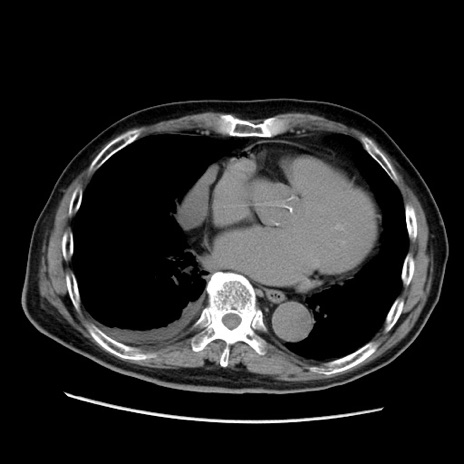

症例21(横断像)

【症例】70歳代男性

【主訴】腹痛

【現病歴】肝硬変・肝細胞癌にてかかりつけの方。約9時間前に食後より腹痛出現。症状が徐々に増悪し、嘔吐出現したため来院。

【既往歴】肝硬変、肝細胞癌(RFA、TACE後)

【身体所見】意識清明、表情苦悶様、BT 36℃、BP 129/78mmHg、P 88bpm、SpO2 97%(RA)、右上腹部から心窩部にかけて圧痛あり、反跳痛なし、筋性防御あり。

【データ】WBC 5800、CRP 0.16